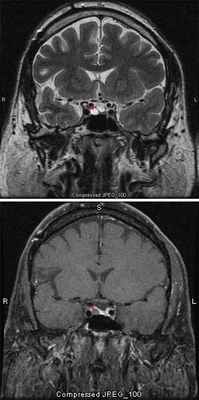

7. Магнитно-резонансную томографию (МРТ) для определения размера, формы и точной локализации новообразования и предположения типа опухоли (табл. 3). МРТ имеет значительные преимущества перед компьютерной томографией (КТ): более качественная визуализация интракраниальных мягких тканей, возможность дифференцировать более тонкие изменения в тканях (отек, изменения сосудов, кровоизлияния и некроз).

Опухоли больших размеров, а также опухоли с ги неринтенсивным сигналом на Т2-взвешенных МРТ-изображениях имеют теп дсниию к росту (70%). R целом Можни сказать, что, как правило, менингиома является показанием к нейрохирургическому вмешательству.

План лечения аденомы гипофиза на КиберНоже. Небольшая красная зона в центре головного мозга, показанного в трех проекциях — это та зона, в которой будет сформирована зона высокой дозы ионизирующего излучения.